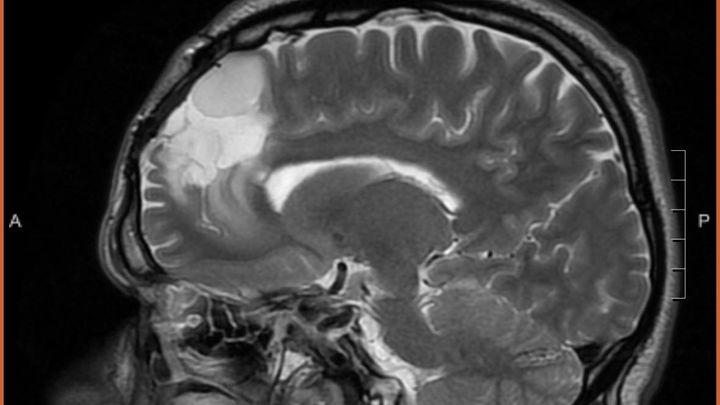

-Derek currently has two potentially deadly infections in his spinal cord, along with IDH Mutant or Astrocytoma, which is a brain cancer that there is currently no cure for. On top of all of this, he has developed 3 masses on and in his liver. With his current regimen of over 20 pills a day, driving to Lexington for appointments 6-8x a week and to Vanderbilt often, as well being a Dad and continuing his duties there, the financial burden has been significant. He has been fighting disability which feels like a losing battle for 2 years. -

Derek has been facing an ongoing battle with brain cancer and other medical issues. Most recently, he learned that he has a severe infection on his spinal cord, a cancerous tumor in his brain, as well as his liver. He has had to have a PICC line put in, and will be down for at least 8-10 weeks, if not longer. Insurance is being a pain and not wanting to cover many parts of his treatment, including home health, which is causing him to have to stay in the hospital, and miss valuable time with his son and best friend, Jayden.